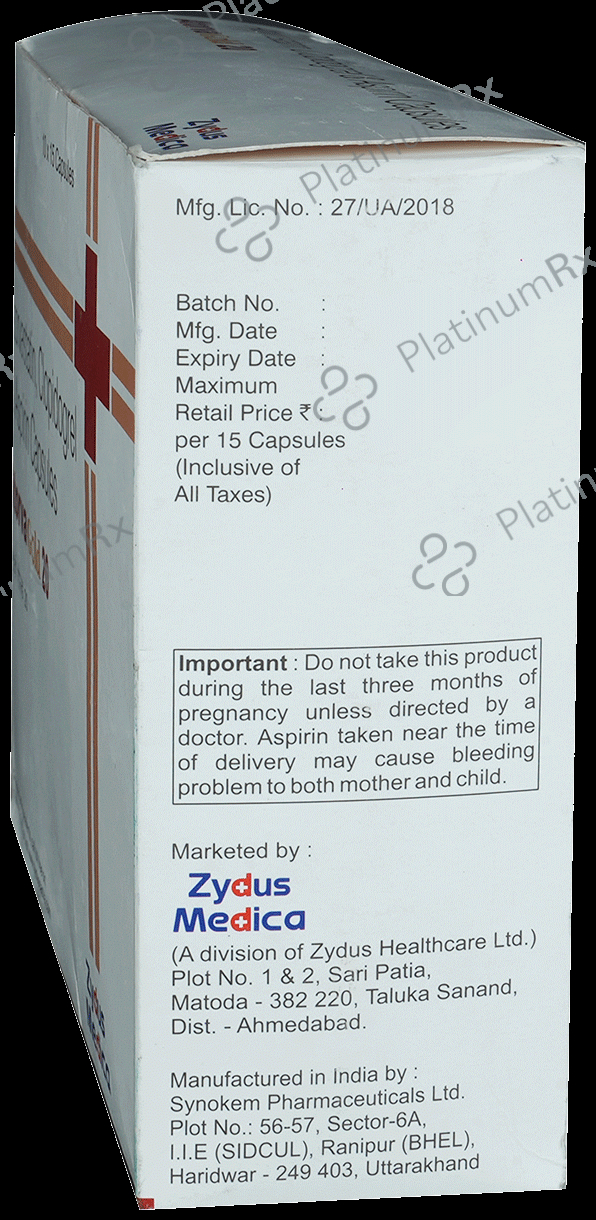

Aspirin 75mg + Atorvastatin 20mg + Clopidogrel 75mg

Salt CompositionAspirin 75mg + Atorvastatin 20mg + Clopidogrel 75mg (same for both)

Atorva Gold 20/75/75mg Capsule 15s

Atorva Gold 20/75/75mg Capsule 15s

Atorva Gold 20/75/75mg Capsule 15s

Zydus Cadila

₹141.1

Atovastrin Gold 75/20/75mg Capsule 15s

Steris Healthcare Pvt. Ltd.

Atovastrin Gold 75/20/75mg Capsule 15s

PlatinumRx is dedicated to delivering dependable and trustworthy information to empower our customers. However, the information presented here is solely for general informational purposes and should not be utilized for diagnosing, preventing, or treating health issues. It is not intended to establish a doctor-patient relationship or serve as a substitute for professional medical advice.